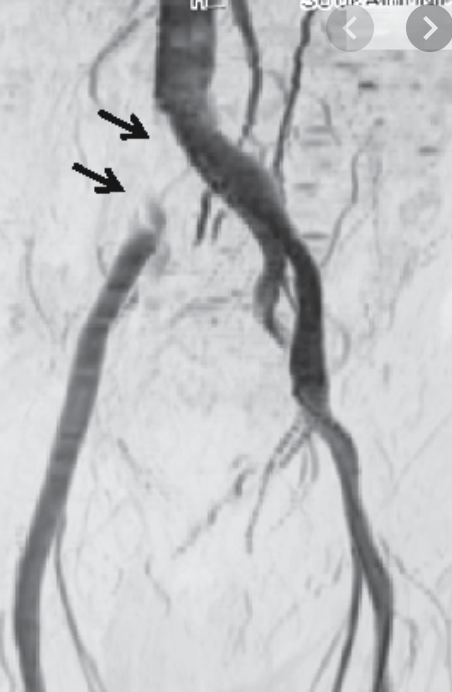

If a patient has had a d-dimer test, wells score and ultrasound and the clinician is still unsure, what test can be performed?